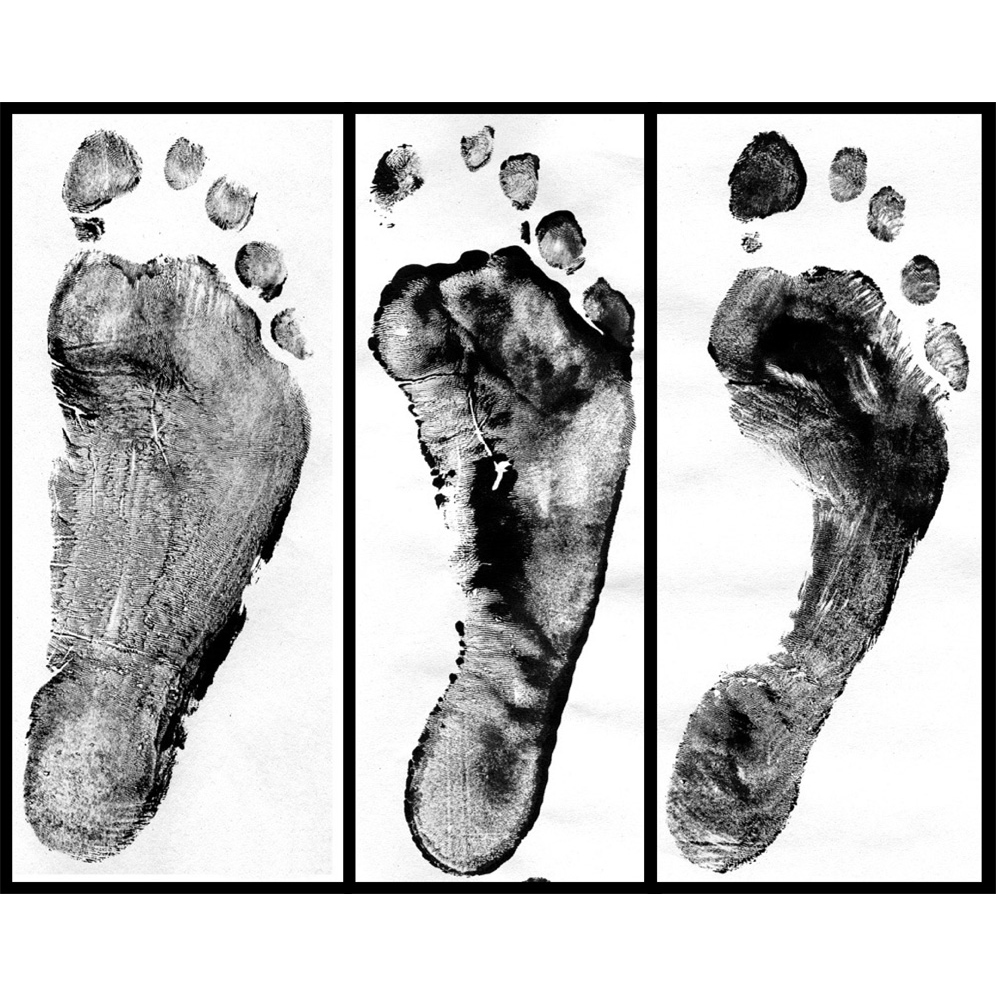

pictures of flat feet

Flat Feet

Flat Feet in Children — Fairfield Podiatry

Flat Foot

set of flat foot, high arch Stock Photo – Alamy